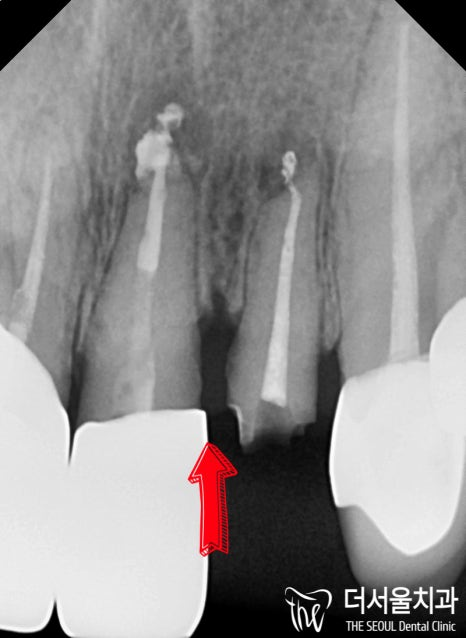

반갑습니다. 잠실 더서울 치과 박현성 원장입니다. 예전에 내원을 하셨던 환자 중에 따님분께 추천을 받아 오게 되었으며, 임플란트 수술을 받았던